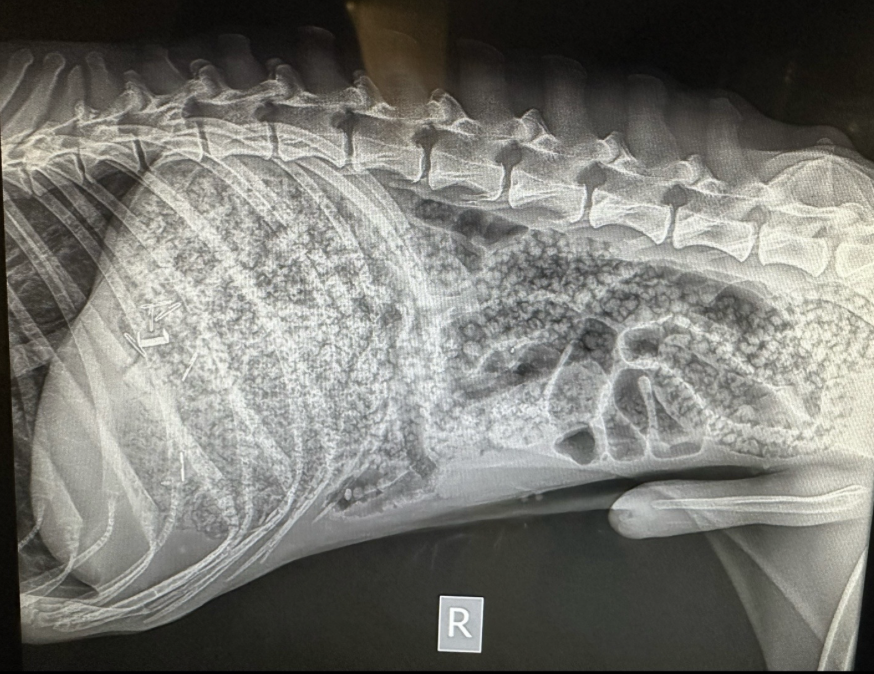

據獸醫診所的X光顯示,狗狗的腸胃幾乎被這些膨脹的小球塞滿!儘管牠通過排便排出了一部分,但大部分仍然滯留在腸胃中,無法自然排出,必須通過手術來清除~這隻狗狗在被救援前是一隻流浪犬,因長期飢餓,所以看到水晶寶寶時才會將其誤認為可以食用的食物~幸運的是,手術非常順利,獸醫成功將這些水晶寶寶從狗狗體內移除!雖然牠依然非常瘦弱,但目前已脫離生命危險,正在慢慢康復中~